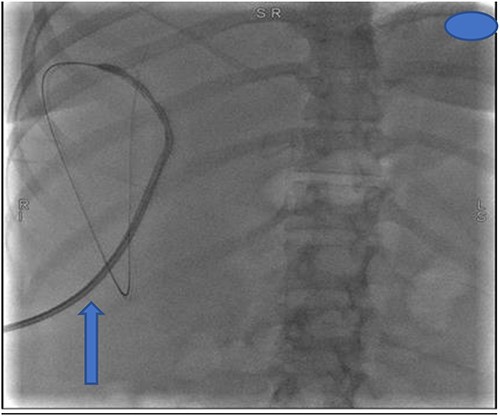

At our facility, ERCP was done. The bile duct was cannulated with 0.035 wire-guided sphincterotome. Cholangiogram showed normal caliber biliary tree with one filling defect in the distal CBD and contrast leak from duct of Luschka to the gall bladder bed (Fig. 1). There was no contrast leak from the cystic duct stump (Fig. 2A). Standard sphincterotomy was performed and a single mulberry stone was removed using stone retreival balloon and double pig tail biliary plastic stent was placed into the RHD and good bile flow was achieved post procedure (Fig. 2B).

(A) First fluoroscopic image shows evidence of no bile leak from cystic duct stump as indicated by the arrows; (B) second fluoroscopic image shows a stent placed into the RHD.